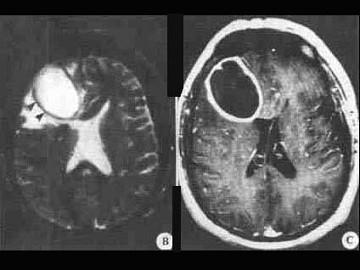

问题 关于脑脓肿(如图所示)下面哪项说法不正确()

选项 A.如在脑脓肿的脓汁中查细菌一定能查到 B.先心病患者可并发脑脓肿 C.耳源性脑脓肿约2/3发生于患耳同侧颞叶 D.脑脓肿的致病菌以金葡萄为常见 E.血液性脑脓肿以额叶、顶叶为多见

答案 A